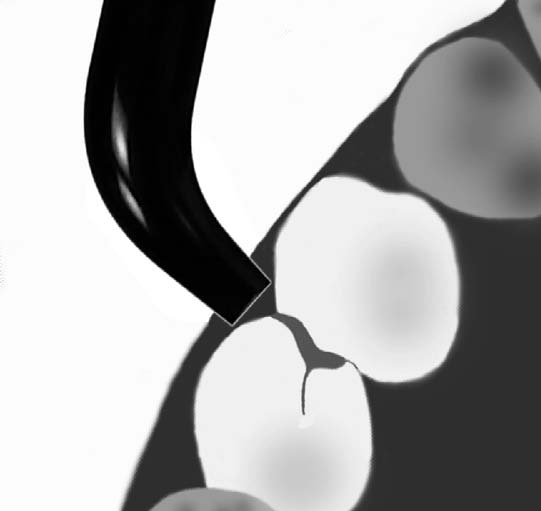

La transiluminación antes de la aparición de la "tecnología

led" solo era utilizada para la detección de caries proximal

en los incisivos. En la actualidad dada la potencia lumínica

de dichos dispositivos puede ser utilizada para la pesquisa

de caries proximal y oclusal de la piezas dentales

posteriores. Se utiliza una lámpara led de luz día ( 5500

ºK) con su fibra óptica, como

se muestra en la fotografía inferior derecha.

La luz visible es enviada por medio de una fibra

óptica hasta la superficie del diente, dónde se propaga

a través del tejido hasta la superficie opuesta. El

resultado es una imagen que resulta de la distribución

de la luz a en el interior d e la pieza dental. (1) Un

proceso de caries en esmalte y dentina tiene la

particularidad de un cuerpo opaco de reflejar la luz, en

consecuencia la observación en la superficie opuesta

generaría una imagen oscura.

En apariencia cuando aplicamos luz,

se mantiene el color gris. Pero

cambiando el eje de luz, podemos ver

el espesor de la sombra gris.

Sospechamos de una caries moderada

por la amplia sombra gris. |